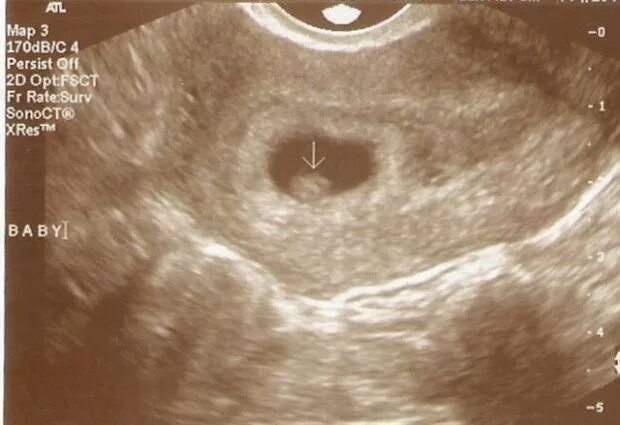

Как выглядит срока